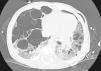

Lactante de 8 meses con dermatitis pápulo-costrosa desde los 3 meses y estancamiento ponderal desde los 5 meses. Ingresa por dificultad respiratoria de 48h de evolución. La radiografía de tórax es compatible con enfermedad intersticial y neumotórax izquierdo. El TC-AR pulmonar muestra múltiples formaciones quísticas bilaterales con neumotórax izquierdo, leve desviación mediastínica y colapso pulmonar izquierdo parcial (fig. 1). Ingresa en la UCI pediátrica para drenaje del escape aéreo. Se realiza biopsia cutánea y lavado broncoalveolar en el que se objetiva un 11,6% de células CD1a mediante citometría, y mediante citología un 20% de las mismas, ambos compatibles con histiocitosis de células de Langerhans (HCL). El resto de exploraciones complementarias no muestran alteraciones significativas. Se inicia tratamiento para HCL sistémica con afectación pulmonar con vinblastina y corticoides.